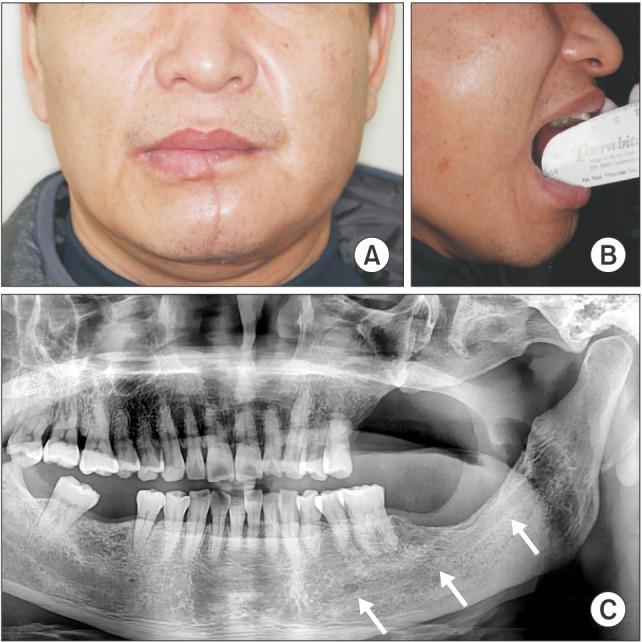

A surgical approach involving the retromolar trigone, posterolateral maxilla, and pterygoid region is the most challenging in the field of maxillofacial surgery. The upper cheek flap (Weber-Ferguson incision) with subciliary extension and the maxillary swing approach have been considered as alternatives; however, neither approach provides sufficient exposure of the pterygoid region and the anterior portion of the mandibular ramus. In this report, we describe two cases in which a lower cheek flap approach was used for complete tumor resection in the retromolar trigone and the anterior mandibular ramus. This approach allows full exposure of the posterolateral maxilla and the pterygoid region as well as the retromolar trigone without causing major sensory disturbances to the lower lip. A mental nerve anastomosis after tumor resection was performed in one patient and resulted in approximately 90% sensory recovery in the lower lip. The lower cheek flap approach provides adequate exposure of the posterolateral maxilla, including the pterygoid, retromolar trigone, and mandibular ramus areas. If the mental nerve can be anastomosed during flap approximation, postoperative sensory disturbances to the lower lip can be minimized.

涉及磨牙后三角、上颌骨后外侧和翼状区域的手术入路是颌面外科领域最具挑战性的。带有睑缘下延伸的上颊瓣(韦伯-弗格森切口)和上颌骨摆动入路已被视为替代方法;然而,这两种方法都不能充分暴露翼状区域和下颌支前部。在本报告中,我们描述了两例采用下颊瓣入路进行磨牙后三角和下颌支前部肿瘤完整切除的病例。这种入路可充分暴露上颌骨后外侧和翼状区域以及磨牙后三角,且不会对下唇造成严重感觉障碍。一名患者在肿瘤切除后进行了颏神经吻合术,下唇感觉恢复约90%。下颊瓣入路可充分暴露上颌骨后外侧,包括翼状、磨牙后三角和下颌支区域。如果在瓣片贴合时能进行颏神经吻合,可将术后下唇感觉障碍降至最低。